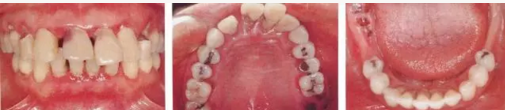

1.png

▲圖16-1~3

11.png

▲圖16-4

▲圖16-1~4 56歲,女性?;加腥谘乐苎浊蚁骂M磨牙區(qū)缺失,可以看到上頜前牙區(qū)有前突的現(xiàn)象。左上1和右上1無法保留。